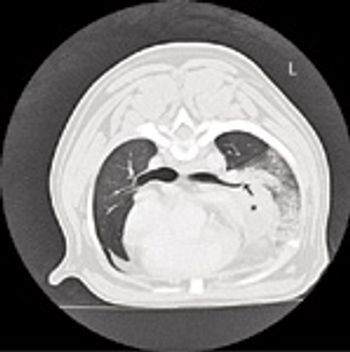

Traumatic thoracic injuries are prevalent in small animals, particularly in dogs.

Traumatic thoracic injuries are prevalent in small animals, particularly in dogs. The most common causes of thoracic trauma are motor vehicular accidents and bite wounds. Other possible, although less common mechanisms include gunshot, knife wounds or being kicked by a larger animal (horse/cow). Injuries may range from mild to life threatening.